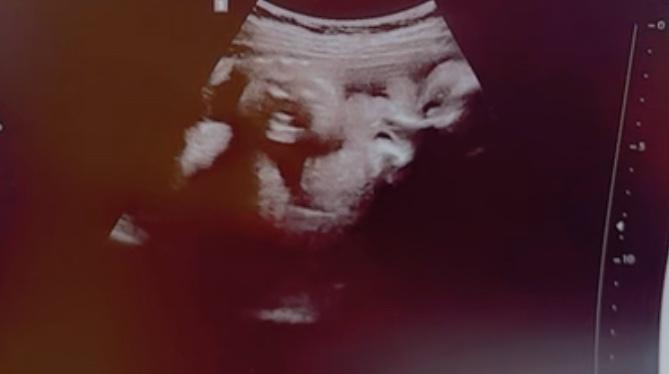

Hayden’s Baby Registry

Arrival date September 23, 2025